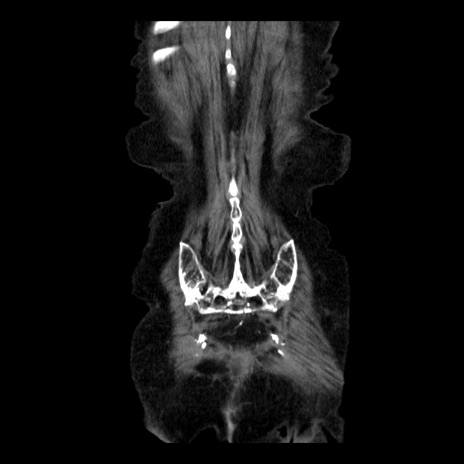

横断像